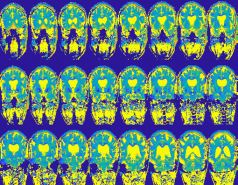

Advanced signal processing techniques